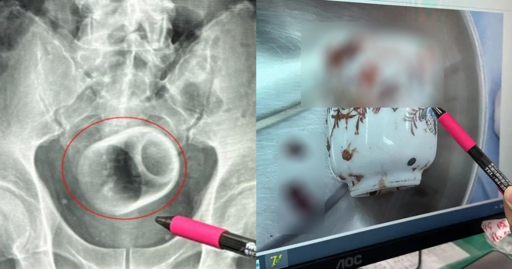

A doctor at the hospital pointed out that while inserting foreign objects into the bottom was not unheard of, they can cause immense damage to internal organs and be fatal.

Things sometimes don’t come out due to shape or they lodge at a weird angle. This increases risk of bowel or rectal perforation as the body tries to push against an obstruction. Think opening a door but a desk is up against it. The cup can also break so now you’ll have ouchie shards that can cut the bowel and create perforations or spill stool into the abdomen. Oh, and cause bleeding.

It’s actually internal muscle movements! Your rectum is divided into two sections my a muscle known as the inner band, which isn’t technically a sphincter but it acts like one. It’s a long loop of muscle that goes around your rectum and anchors to the torso. When you have to shit, it relaxes and allows poop into your lower rectum. If you decide to hold it, after a couple minutes, it moves the poop back into your upper rectum and you stop getting the urgent urge to shit. However, your rectum doesn’t discriminate, and will attempt to pull foreign objects deeper as well.

When you push shit out, you’re compressing that bottom section of your rectum to push shit out. (This is something you can feel for yourself if you want to stick a finger or two up your butt) You can’t do the same motion with the top of your rectum, so you can’t push things out of it. The inner band is hard to manipulate with external tools/your fingers. Like sure you can reach in there and stretch it a bit, but far enough for a large object to drop out isn’t going to happen. If the object is too large and your inner band too tight, it’s going to be extremely difficult to get out. Shit is going to back up behind it instead of pushing it out.